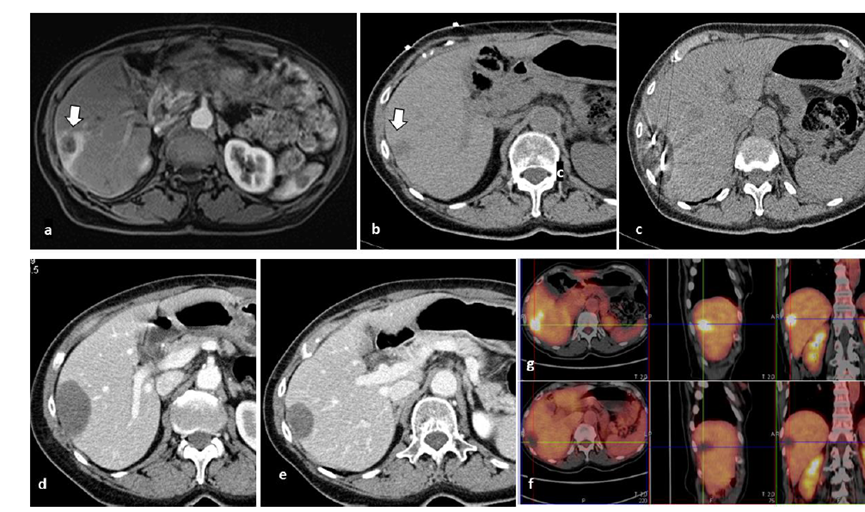

冷凍消融膽囊附近腫瘤病灶

(A)動脈期 MRI 顯示膽囊附近有外周增強病變(箭頭)。

(B)手術(shù)過程中 CT 顯示冷凍探針位于病灶內(nèi)。

(C)消融后,術(shù)后 1 個月CT 顯示完全消融(箭頭)。

79 歲男性,肝轉(zhuǎn)移(結(jié)直腸癌)腫瘤的完全消融病例

( a ) 軸向 MRI 和 ( b ) 軸向 CT 顯示肝S8段有一個16mm的病灶,鄰近肝緣。( c )冷凍消融期間CT顯示放置了2個冷凍探針,低密度冰球包圍病灶。(d)術(shù)后1個月隨訪 CT顯示冰球?qū)?yīng)的壞死區(qū)域,未見復(fù)發(fā)。(e)術(shù)后6個月的CT,壞死區(qū)域縮小,未見復(fù)發(fā)。(f)與基線影像(g)相比,12個月后的FDG-PET/CT顯示未見FDG攝取。

62歲女性,肝轉(zhuǎn)移(卵巢癌)腫瘤的完全消融病例(a)軸向CT顯示病變位置毗鄰心臟和上腔靜脈(黑色箭頭)。(b)術(shù)中軸向CT掃描:使用三個冷凍探針。1個月后的軸向(e)和冠狀位(f)增強CT掃描顯示低密度區(qū)域,由于肉芽組織反應(yīng)引起的邊緣增強。